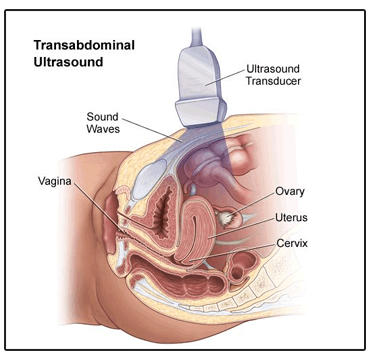

1. Transabdominal ultrasound:

An abdominal ultrasound is a regular scan that allows the doctor to examine the uterus, cervix, ovaries, bladder and fallopian tubes. This scan is mostly done before the transvaginal ultrasound so the doctor can determine if it is safe to conduct a transvaginal exam without disrupting or damaging the low placenta.

How it is done:

An ultrasound transducer (a probe that can help in imaging) is gently pressed against the abdomen along with a gel. The sound waves from the transducer bounce off the organs and fall back into the transducer which then converts the sound waves into a video through a computer.